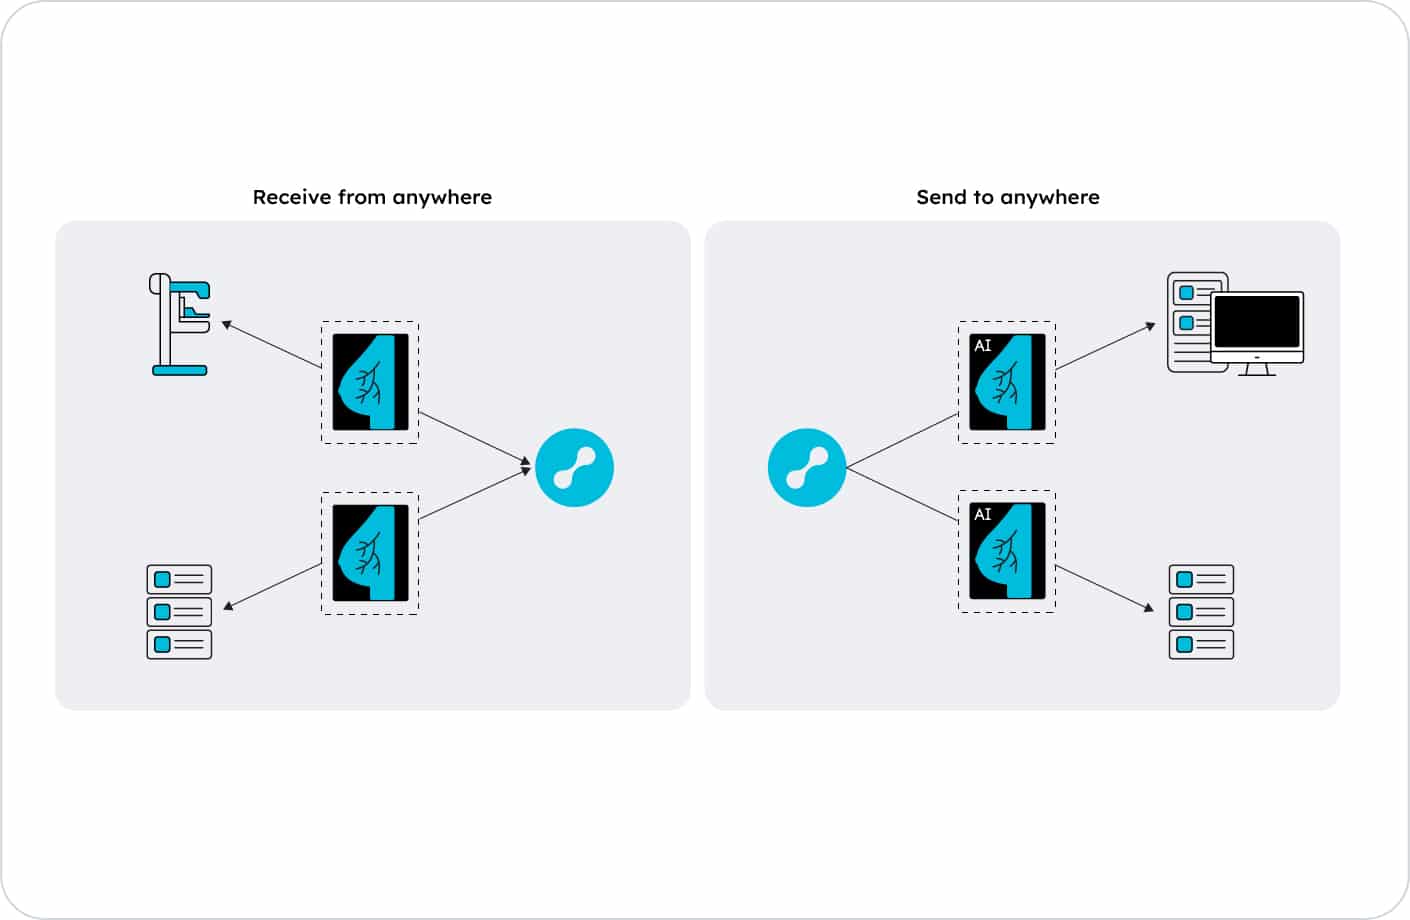

At Lunit, we believe innovation is most powerful when it’s collaborative. That’s why we work with leading imaging manufacturers, PACS/RIS vendors, and digital health platforms to deliver AI-powered radiology solutions that fit seamlessly into real-world clinical workflows.

Built for enterprise-scale healthcare systems, our AI ecosystem meets the technical, regulatory, and operational demands of modern radiology networks.

Our partner-first approach enables rapid, secure, and stable integration of Lunit’s AI solutions into the existing radiology environments.

With flexible deployment options and dedicated technical support, Lunit’s AI fits naturally into clinical workflows—without any disruption.